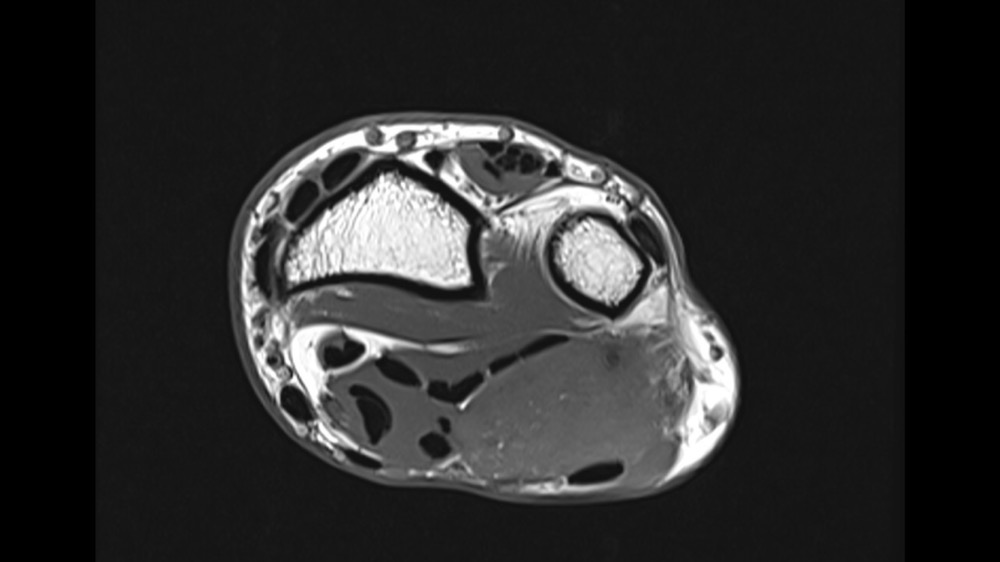

Bone Club

Thomas Leclerc 23/03/2022